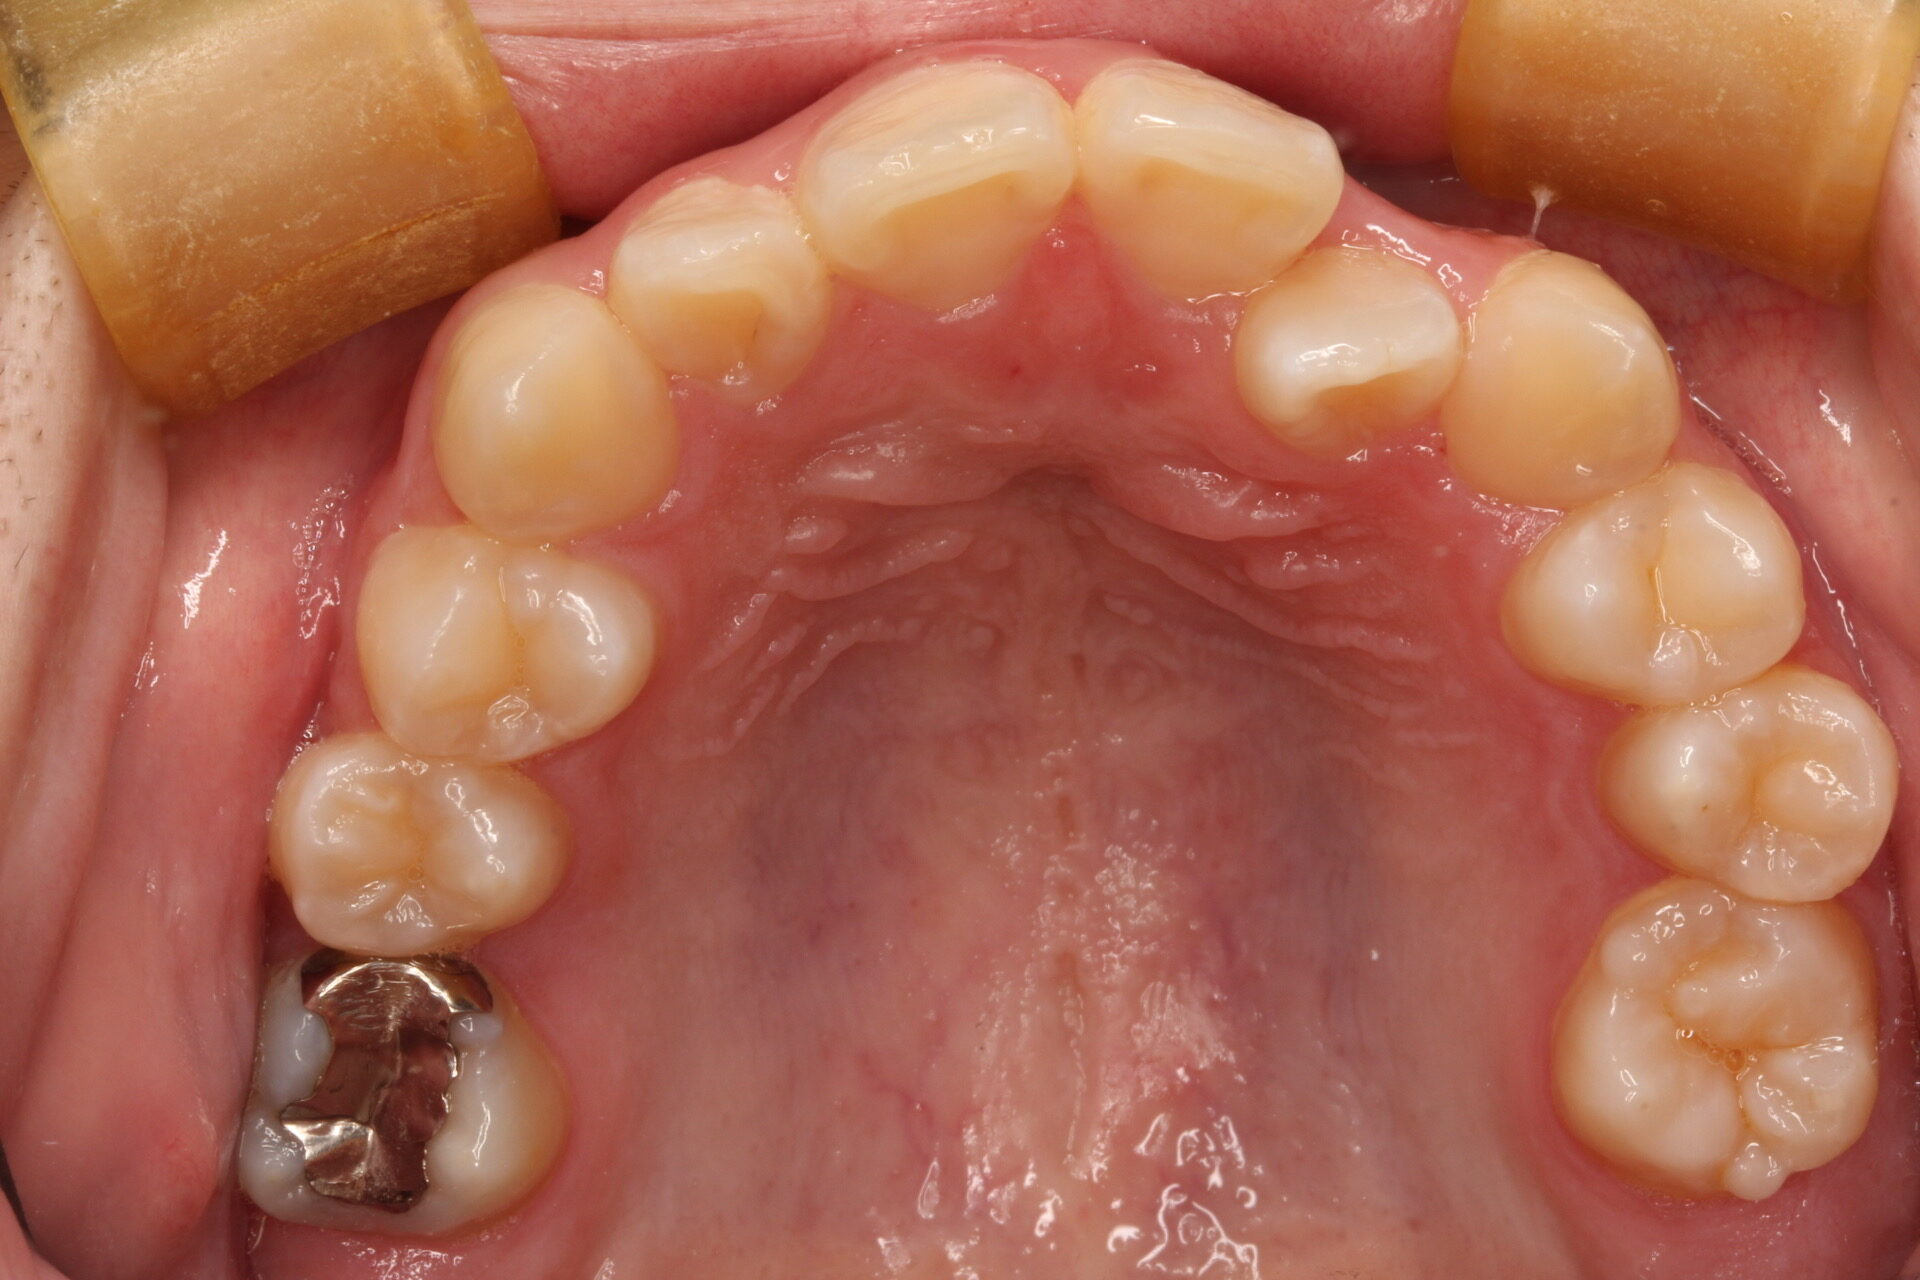

矯正術前:上顎

矯正術後:上顎